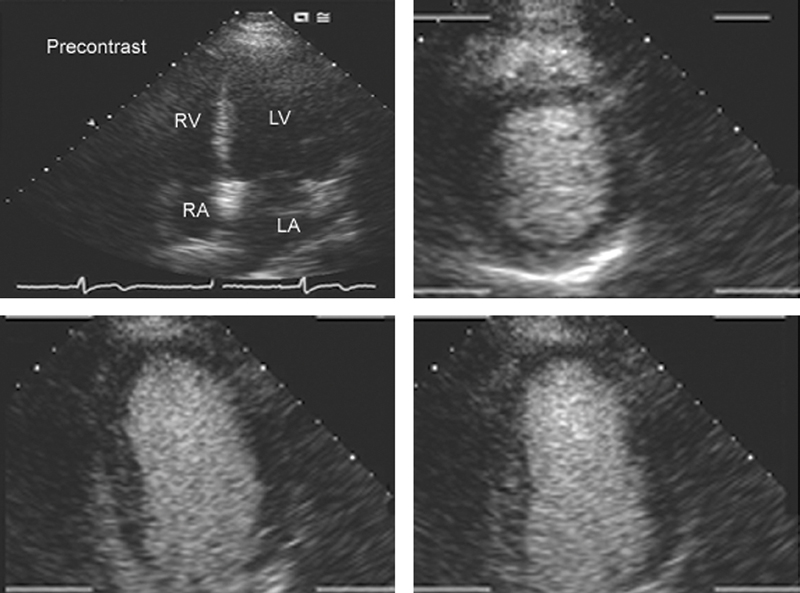

فحوصات تشخيصية لبعض امراض القلب والشرايين التاجية